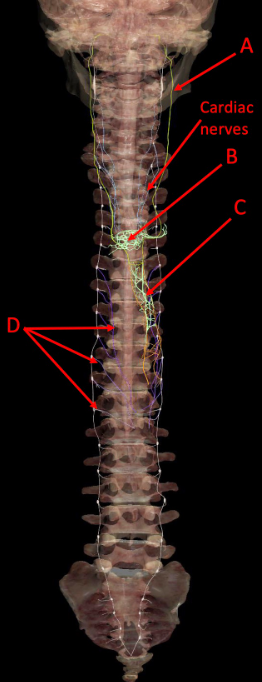

Identify the following structure(s)

A

A. left vagus nerve

B. cardiac plexus

C. esophageal plexus

D. thoracic splanchnic nerves (greater, lesser, least)